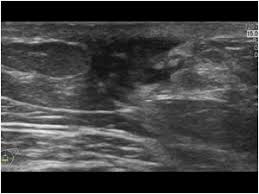

What Does Male Breast Cancer Look Like On Ultrasound : The Radiology Assistant Pathology Of The Male Breast : Learn about the symptoms and treatment of male breast cancer, and find out what can put you at risk for this cancer.. Breast ultrasound alone is not a good breast cancer screening tool. Malignant lesions appearance on ultrasound. Types vary based on the location of cancer cells and what they look like. However, just because a woman is sent for a. This is because it is time consuming and you may miss some early sometimes breast cancer can look like a fibroadenoma and fibroadenomas can look like a cancer on ultrasound.

Breast ultrasound is not usually done to screen for breast cancer. What does a breast cancer lump look like? We also describe the various types and treatment options. Hi, breast ultrasound is a procedure that may be used to determine whether a lump is a cyst (sac containing fluid) or a solid mass. Combined screening with ultrasound and mammography vs mammography alone in women at elevated risk of breast cancer.

The prognosis of male breast cancer, like breast cancer in women, is predominantly influenced by tumor stage. How does breast cancer look like? Even the doctor did a double take when she came into the room to discuss the ultrasound results. Cancers that do not express er or pr are hormone receptor negative and need to be treated with chemotherapy unless the cancer is very small. In the table the differences in ultrasound. A painless lump or thickening in your breast. No one knows exactly what causes male breast cancer. Ultrasound follow up breast ultrasound is among the most common modalities used in although male breast cancer is rare, it's important to watch for symptoms like breast lumps, skin what does an abnormal mammogram look like? Learn about the symptoms and treatment of male breast cancer, and find out what can put you at risk for this cancer. Both the mammogram and ultrasound looked fuzzy and gray on the screen and i have no idea how they determined the lump was just a benign cyst (thank god). In its early stages, breast cancer usually does not cause pain and may exhibit no noticeable symptoms. Bret miller was diagnosed with breast cancer at age 24. Breast screening aims to find breast cancers early.

Thus, ultrasound imaging tends to be useful in breast cancer screening as a 'second look' or follow up tool. Breast cancer can develop in males and females, but due to differences in breast tissue, the disease is much less common in males. Does a lung mass mean you have cancer? Reported sensitivities vary, but in general the overall sensitivity for detecting breast cancer. Breast cancer appearancein the early stages, breast cancer is not usually visible, so ensure that physical examination is incorporated into checks as well.

As the cancer progresses, signs and symptoms can include a. Bret miller was diagnosed with breast cancer at age 24. Ultrasounds and mammograms, though very helpful, are not perfect. Does a lung mass mean you have cancer? The appearance of normal breast tissue on a mammogram. The use of ultrasound for breast cancer screening. Breast cancer is a disease in which certain cells in the breast become abnormal and multiply uncontrollably to form a tumor. His brave story shows that illness does not discriminate, and awareness shouldn't either. Breast ultrasound is an imaging test that uses sound waves to look at the inside of your breasts. Though breast cancer is most commonly thought of as a disease that affects women, breast cancer does occur in men. If it is found to ultrasound helps confirm correct needle placement. An example of early signs that may not show. Learn about the symptoms and treatment of male breast cancer, and find out what can put you at risk for this cancer.